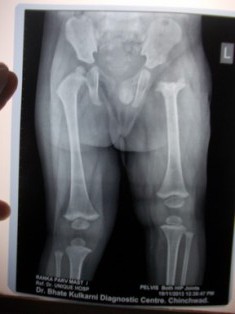

Child not moving any part of the limb should be suspected as having septic arthritis unless proven otherwise. The child will have pain on active and passive movement of the limb. Risk factors include low birth weight, NICU stay, umbilical vein catherization and central venous catheters. Joints commonly involved are hip, knee, elbow and ankle. Diagnosis of a joint infection is difficult because the child may not have abnormal blood test, may not have a high fever. Soft tissue ultrasound will usually reveal the diagnosis. Bone scan can be performed if ultrasound is negative and there is strong suspicion of osteomyelitis. MRI may be required in some cases to diagnose infection. Surgical management: Infections within a joint require prompt treatment in form of arthrotomy to prevent possibly permanent damage to joint cartilage.